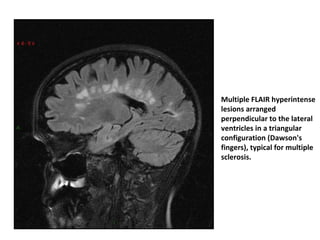

• Dawson’s Fingers:

– Dawson fingers are a radiographic feature

depicting demyelinating plaques through the

corpus callosum, arranged at right angles to

ventricles along medullary veins (callososeptal

location).

– It is probably associated with the inflammatory

changes around the long axis of the medullary

vein that create the dilated perivenular space.

– They are a relatively specific sign for multiple

sclerosis (MS), which presents as T2 and FLAIR

hyperintensities.

Multiple FLAIR hyperintense

lesions arranged

perpendicular to the lateral

ventricles in a triangular

configuration (Dawson's

fingers), typical for multiple

sclerosis.

• Dawson’s Fingers: –Dawson fingers are a radiographic feature  depicting demyelinating plaques through the  corpus callosum, arranged at right angles to  ventricles along medullary veins (callososeptal  location). – It is probably associated with the inflammatory  changes around the long axis of the medullary  vein that create the dilated perivenular space. – They are a relatively specific sign for multiple  sclerosis (MS), which presents as T2 and FLAIR  hyperintensities.

Multiple FLAIR hyperintense lesionsarranged perpendicular to the lateral ventricles in a triangular configuration (Dawson's fingers), typical for multiple sclerosis.